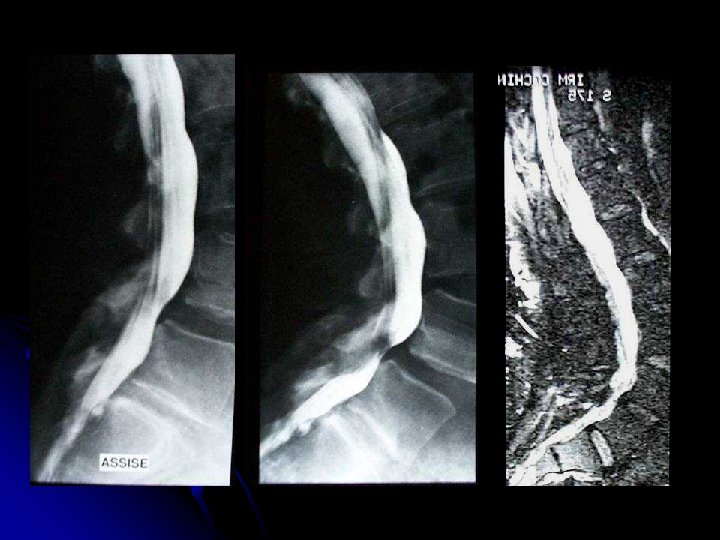

MYÉLO-IRM / TECHNIQUE l ANTENNE DE SURFACE «PHASED ARRAY» l MEMBRES INFÉRIEURS EN EXTENSION

MYÉLO-IRM / TECHNIQUE l ACQUISITION CORONALE l PRÉSATURATION DE LA GRAISSE l SÉQUENCE FSE TRÈS PONDÉRÉE T 2 l TE 140, 1 EX, ETL 48 l MATRICE 512 X 256 l FOV 30

MYÉLO-IRM / TECHNIQUE l ÉPAISSEUR COUPE 1. 5 mm l 8 COUPES/ PILE l 10 PILES l PUIS, MIP FRONTAL, OBLIQUE, SAGITTAL